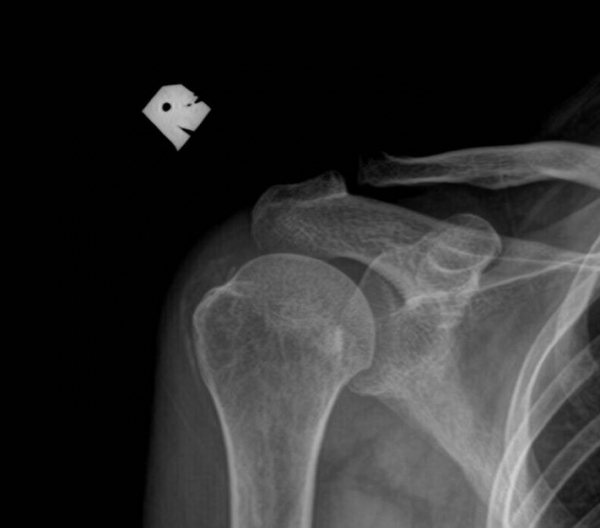

¹æ»ç¼± °Ë»ç :  ÃÊÁø ½Ã ¹æ»ç¼± °Ë»ç¿¡¼­ ¾çÃø ±Ø»ó°Ç°ú °ß°©Çϱٰǿ¡ Å« ¼®È¸°¡ °üÂûµÈ´Ù(»çÁø 8. 9).

Ä¡·á ÈÄ ¾à 1´Þ ÈÄ¿¡ ÃßÀû °Ë»çÇÑ »çÁø¿¡¼­  ¿ìÃø ±Ø»ó°Ç ¼®È¸´Â °ÅÀÇ ¼Ò½ÇµÈ ¸ð½ÀÀ̰í

ÁÂÃø ±Ø»ó°ÇÀÇ ¼®È¸´Â ¸¹ÀÌ ÁÙ¾îµç ¸ð½ÀÀÌ´Ù(»çÁø  10. 11).